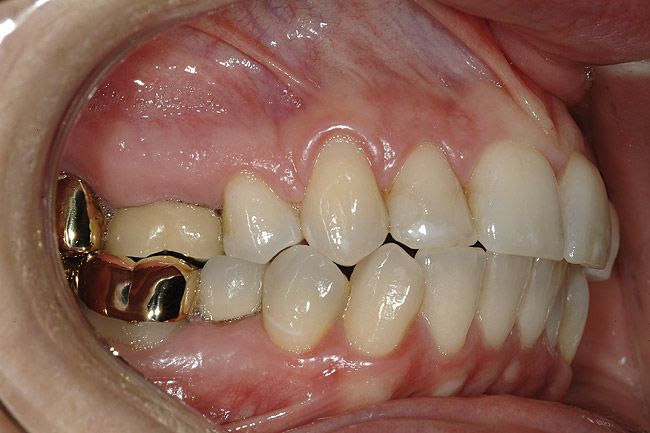

FUNCŢIONAL: La majoritatea dinţilor posteriori ai pacientei ce erau restauraţi cu coroane (fig. 6, 7) era importantă interpretarea minuţioasă a istoricului pacientei şi a rezultatelor evaluării ocluzale. Coroanele din aur de la nivelul 1.7. şi 1.4. prezentau orificii de uzură pe suprafeţele ocluzale, cu semne de minimă uzură pe celelalte coroane posterioare şi la dentiţia naturală. Era evidentă o uzură moderată pe coroana din aur a molarului 4.7.

Traumatismul ocluzal primar s-a observat la dinţii 1.5. şi 2.5. În intercuspidare maximă, s-a notat ocluzie deschisă la segmentele dentare frontale 1.3.-2.3. şi 3.3.-4.3. Dinţii 1.6. şi 4.6., precum şi 2.6. şi 3.6. erau în angrenaj invers (fig. 5, 8). Pacienta prezenta o ocluzie Angle Clasa I. Având în vedere rezultatele istoricului şi examinării s-a stabilit un diagnostic de disfuncţie ocluzală.

DENTO-FACIAL: Evaluarea zâmbetului pacientei a evidenţiat o dinamică labială maxilară medie şi afişarea ţesuturilor la zâmbire (fig. 2). Nivelurile gingivale maxilare inegale, exostoza osoasă vestibulară vizibilă corespunzător 1.6., dinţii rotaţi sau malpoziţionaţi, coloraţia de pe mai mulţi dinţi frontali, o „linie a surâsului inversată” , asimetria dentară şi un plan ocluzal maxilar neregulat reprezentau puncte semnificative în cadrul evaluării dentofaciale. Dorinţa pacientei de a avea un zâmbet ideal sau „generat de media” a accentuat dificultatea cazului. Dinamica labială maxilară medie şi afişarea în consecinţă a ţesuturilor a dictat evaluarea riscului pentru acest caz.